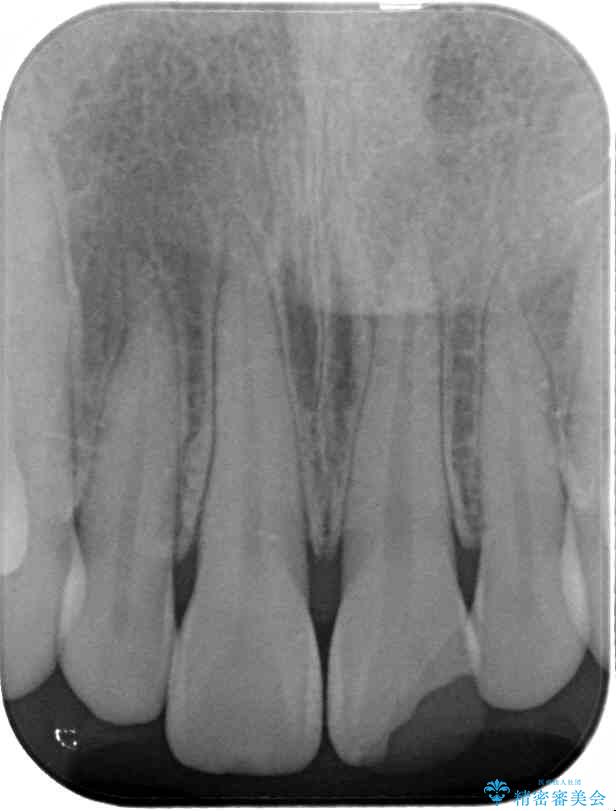

神経を取り除いたことで変色した前歯を気にして来院された患者様です。

根管治療はやり直さずに、ファイバーポストを使用した土台を植立してオールセラミッククラウンにて補綴することとしました。

治療前

• 変色した前歯をオールセラミッククラウンに 治療前画像